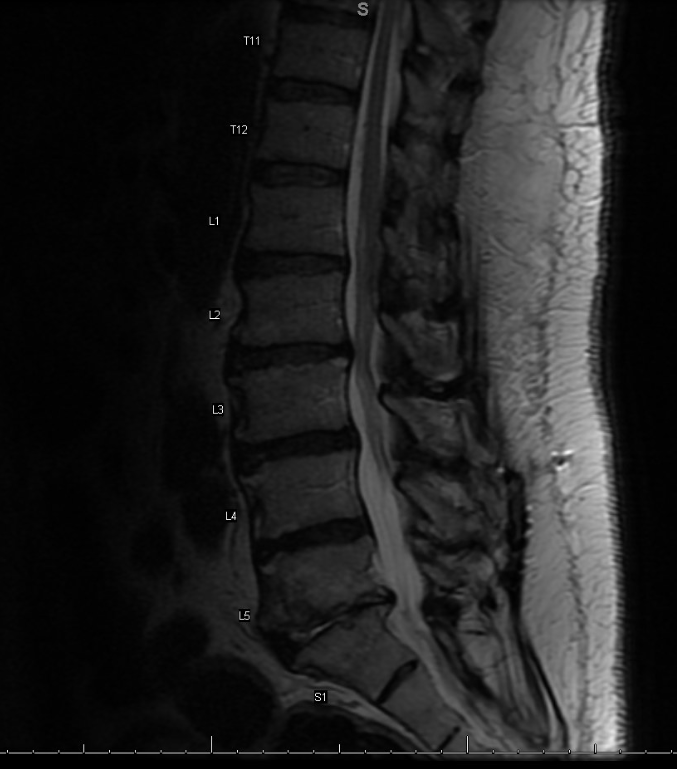

Case Presentation: A 73 year old male with a history of hypertension and osteoarthritis presented to the hospital with progressively worsening back pain. He has chronic back pain, but suddenly woke up and noticed a difficult time walking and standing, resulting in a fall. His symptoms were associated with subjective fevers, chills, and diaphoresis. Vital signs revealed high grade fever, tachycardia, tachypnea, and hypotension. Laboratory findings revealed leukocytosis and lactate elevation. He received intravenous hydration, empiric antibiotics, and an infectious workup was started. Urinalysis, chest radiograph, CT abdomen, pelvis, and CT spine were negative for any acute or infectious process. Blood cultures grew pan-susceptible Proteus mirabilis. Antibiotics were de-escalated to Ceftriaxone. Given his persistent back pain, MRI of his spine was obtained which revealed L5-S1 and T10-T11 endplate enhancement suggesting multifocal early discitis and osteomyelitis. Blood cultures cleared after three days of Ceftriaxone and he remained afebrile. The patient was discharged with plans to complete 6 weeks of antibiotic therapy.